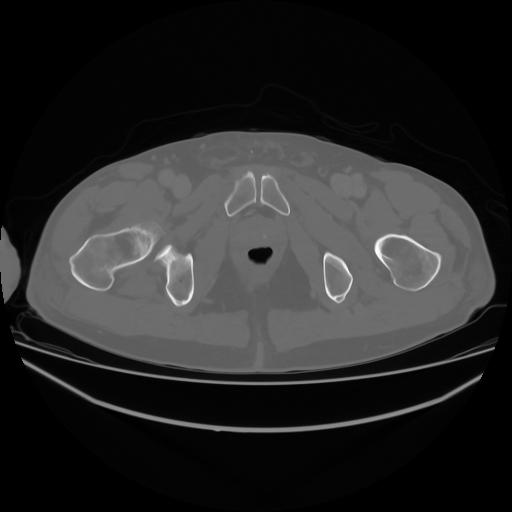

4 CUERPO,CE,Axial,3.0,CUERPO,,